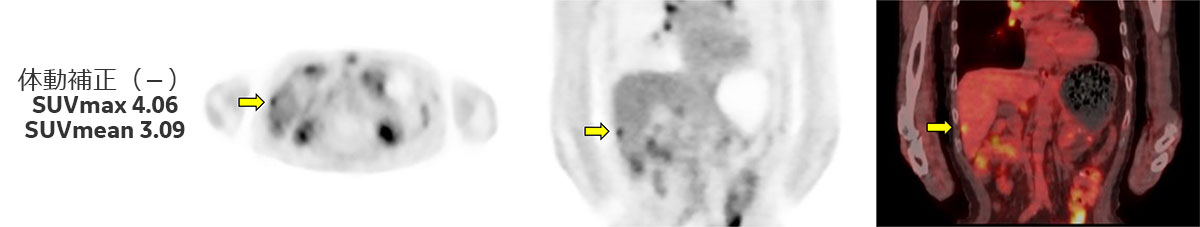

また、Discovery IQ2.0ではデバイスレスの体動補正であるAdvanced MotionFreeが搭載されており、PET画像とCT画像の位置ずれ軽減、診断精度の向上が期待できます。

上記とは別症例になりますが(Fig.4)、体動補正を行う事で病変部がより明瞭となっているだけでなく、SUV測定結果では体動補正無しでSUVmax 4.06、SUVmean 3.09だったものが、体動補正を行う事によりSUVmax 5.71、SUVmean 4.06とSUVの上昇も認められています。